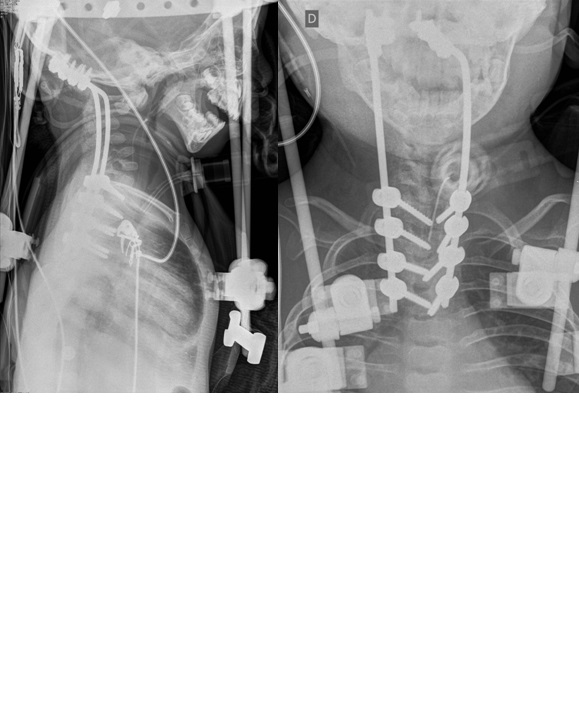

- Figura 10. Imágenes Postoperatorio inmediata: fusión occipito torácica más halo chaleco

- Figura 11. Imágenes Radiográficas 2 años postoperatoria